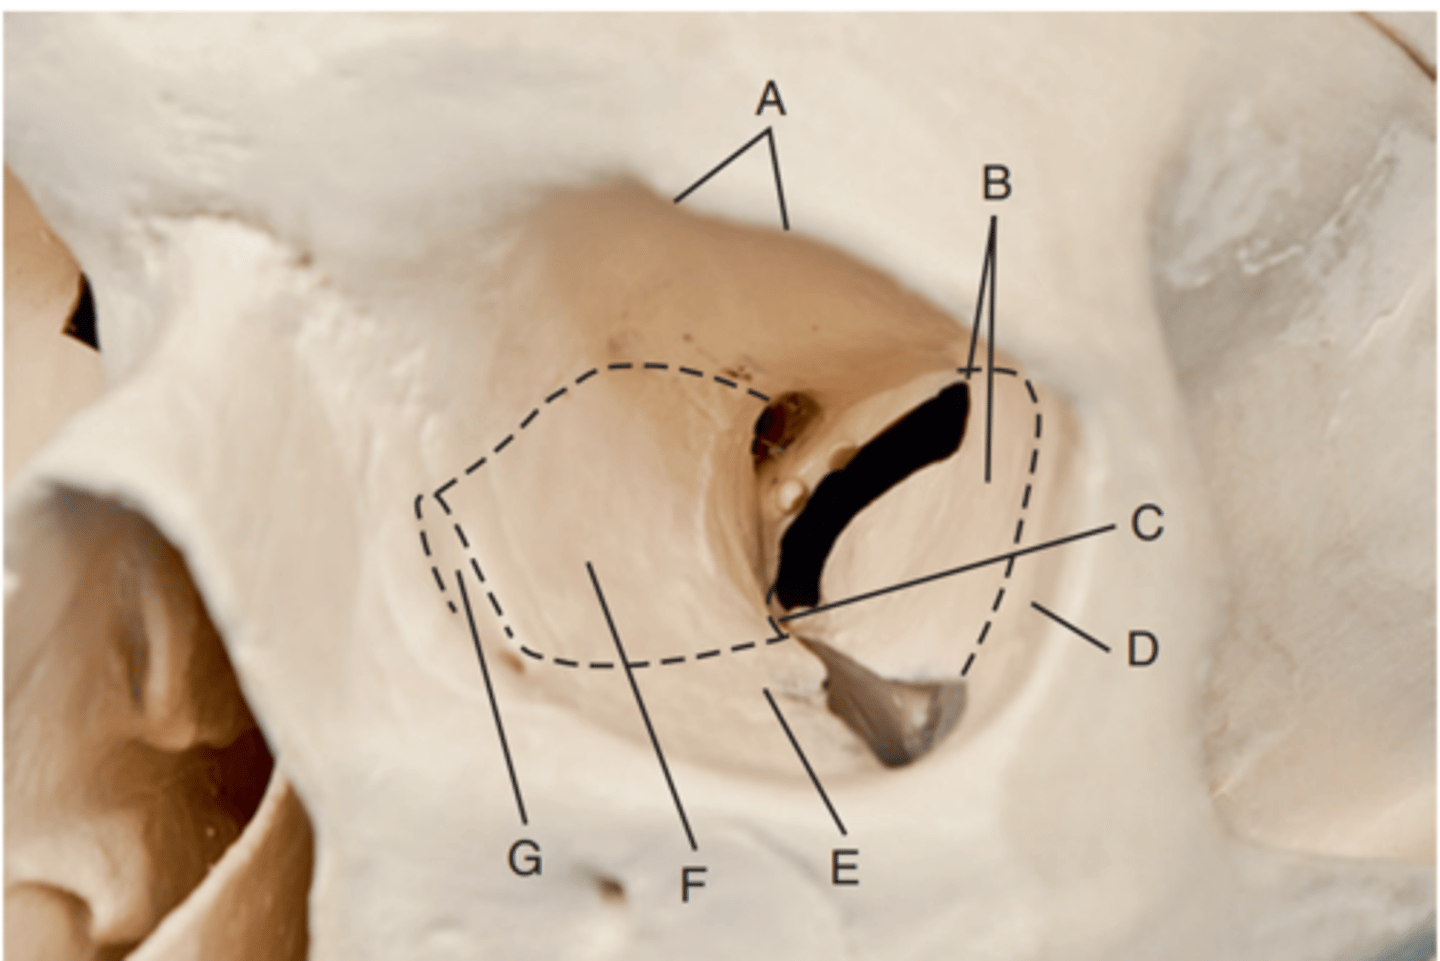

Optic foramen

Label A

Sphenoid strut

Label B

Superior orbital fissure

Label C

Inferior orbital fissure

Label D

Orbital plate of frontal bone

Label A

Sphenoid bone

Label B

Optic foramen and canal

Label C

Superior orbital fissure

Label D

Infraorbital margin (IOM)

Label E

Sphenoid strut

Label F

Lateral orbital margin

Label G

Supraorbital margin

Label H